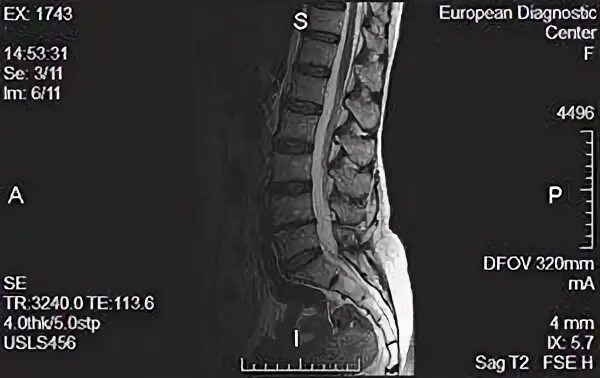

Мрт брянск бежицкий